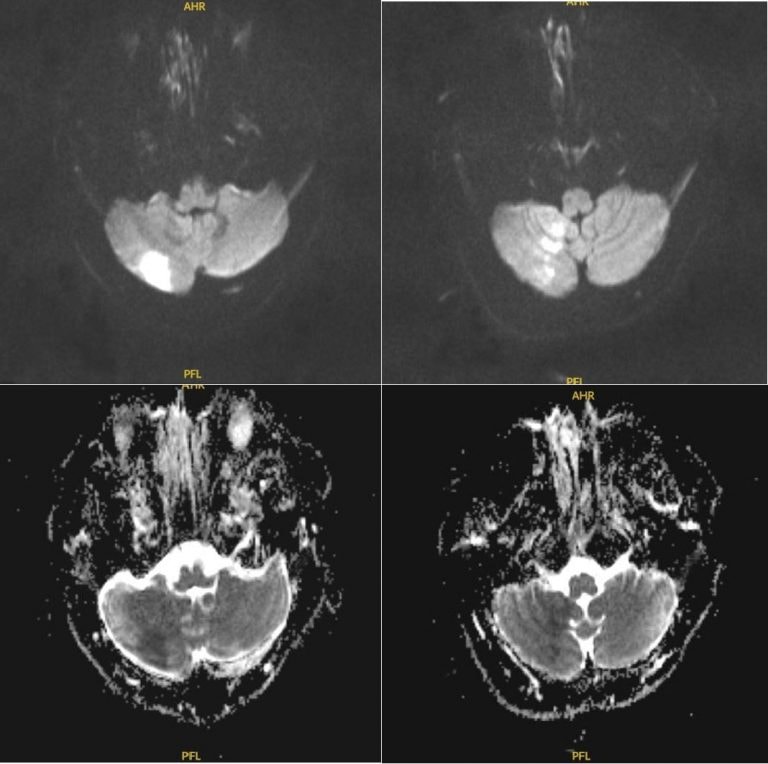

Tại khoa Cấp cứu của bệnh viện, sau khi thăm khám, các bác sĩ nghi ngờ đây là triệu chứng của một cơn đột quỵ. Ngay lập tức, người bệnh được tiến hành chụp MRI, kết quả xác định có vùng nhồi máu tiểu não bên phải.

Bệnh nhân được kiểm soát huyết áp, tiêm thuốc tiêu sợi huyết (rTPA) qua đường tĩnh mạch có tác dụng tái thông mạch máu đang bị tắc nghẽn, giúp cấp máu và oxy kịp thời cho các tế bào não đang có nguy cơ bị tổn thương nghiêm trọng.

Ngay khi tiêm thuốc, bệnh nhân đã giảm chóng mặt nhanh chóng, giảm thất điều, không ghi nhận hẹp hay tắc mạch máu lớn trên phim CT mạch máu não. Sau đó, người bệnh được tiếp tục điều trị, theo dõi và tầm soát các căn nguyên đột quỵ. Sau 7 ngày, bệnh nhân đã được xuất viện.